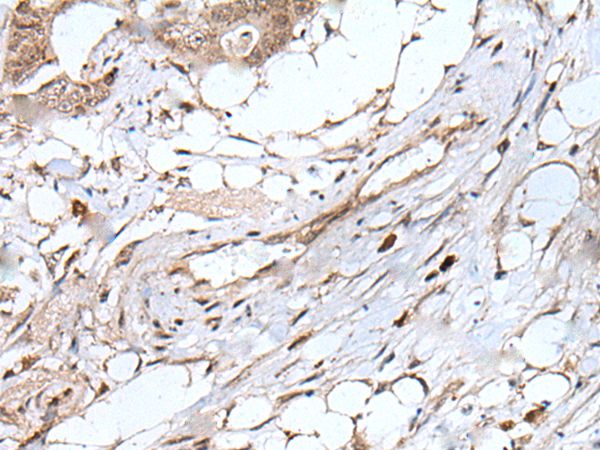

The image on the left is immunohistochemistry of paraffin-embedded Human cervical cancer tissue using UBN1 Antibody at dilution 1/100, on the right is treated with synthetic peptide. (Original magnification: x200)

The image on the left is immunohistochemistry of paraffin-embedded Human colorectal cancer tissue using UBN1 Antibody at dilution 1/100, on the right is treated with synthetic peptide. (Original magnification: x200)